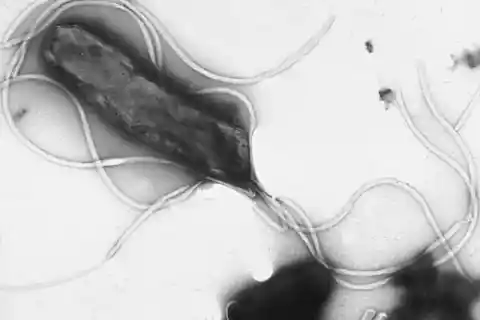

Historias destacadas en la categoría Salud

Descubre las publicaciones más recientes dentro de Salud.